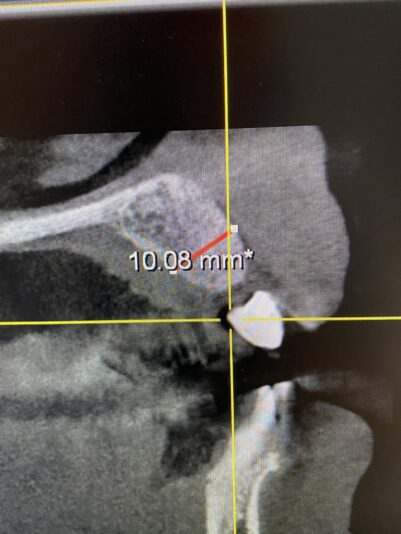

• Looks good, right?!? Not once you see the cbct and create a larger full thickness flap. What would you do here? What are your options? This happened during one of our live surgery courses. Please leave a comment below on what you would do and a couple options we may have. After I recieve several comments I will post a follow up post next week…

Read more

• implant position looks too buccal to me in this photo. i’d remove and start a new osteotomy and sink the implant to the level of the lingual bone